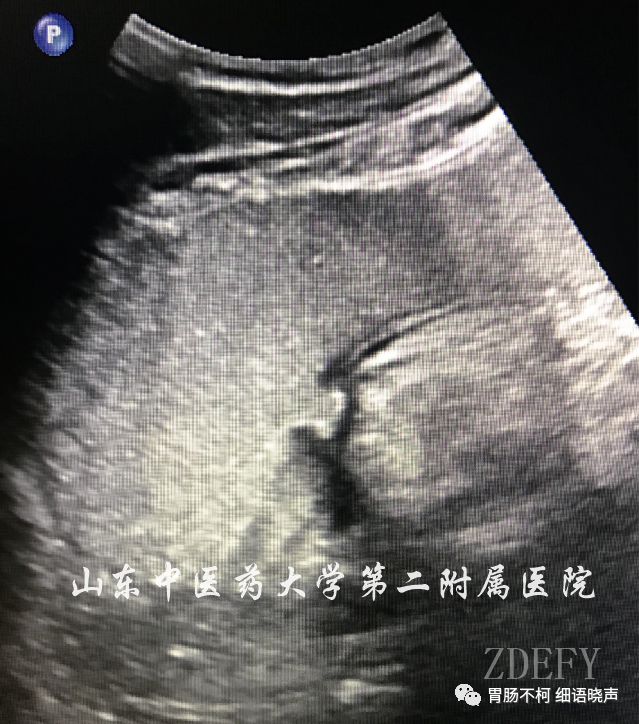

“平地挖坑征”是良性溃疡的征象。良性溃疡是宛若平地的胃壁炎症基础上的破损凹陷,就像直接在平地挖了个坑,故名“平地挖坑征”。溃疡底部较平整。典型病例如下: